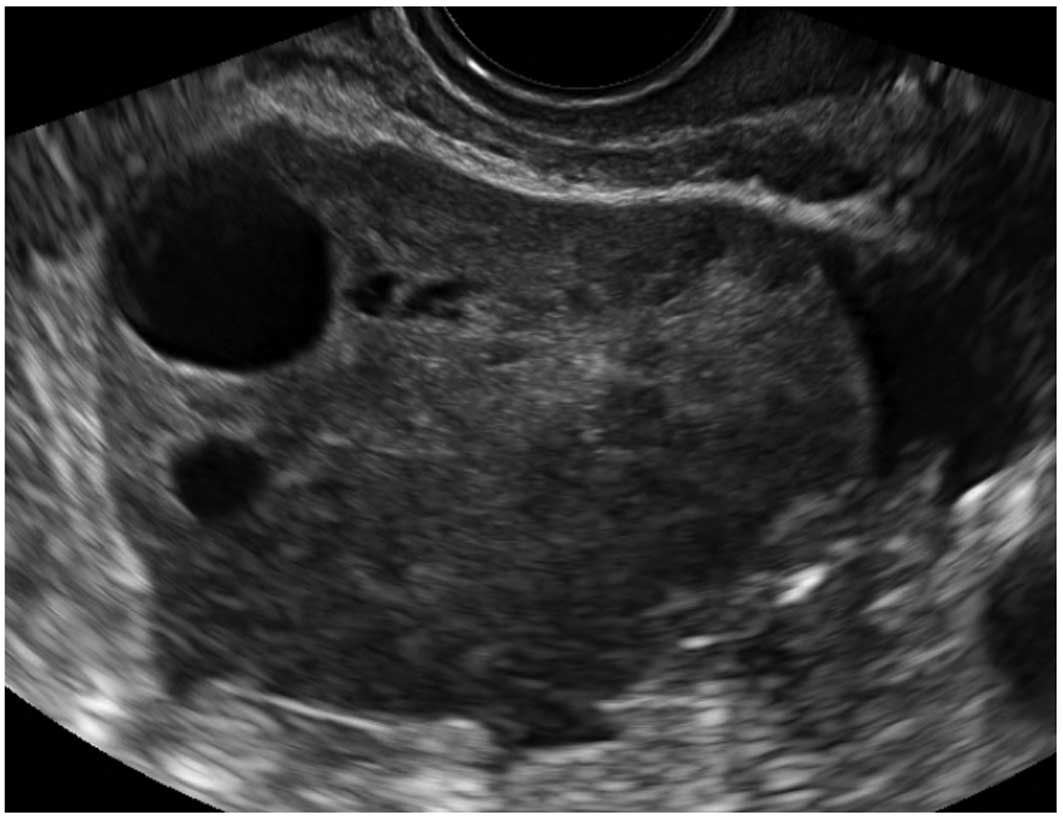

В процессе гинекологического УЗИ точно устанавливаются размеры кистомы, толщина капсулы, уточняется наличие камер и сосочковидных разрастаний. При пальпации живота, а также с помощью УЗИ брюшной полости может выявляться асцит. Обнаружение опухоли яичника требует исследования онкомаркера СА-125. В ряде случаев для уточнения диагноза целесообразно проведение КТ или МРТ малого таза. Окончательное подтверждение диагноза и выяснение морфологической формы папиллярной кистомы яичника производится в процессе диагностической лапароскопии, интраоперационного гистологического исследования.

Объемное образование яичника может быть обнаружено врачом при осмотре, однако диагноз кисты устанавливается при ультразвуковом исследовании. По тем или иным ультразвуковым признакам можно с определенной вероятностью предположить тот или иной тип кисты яичника.

При кистах, проявляющихся болями, нарушением функции яичников,продолжающих существование более 2 циклов, и не имеющих признаков опухолевого процесса, возможна пункция и аспирация под контролем ультразвукового сканирования[1]. При этом с помощью вагинального ультразвукового датчика и пункционной насадки в полость кисты вводят иглу.